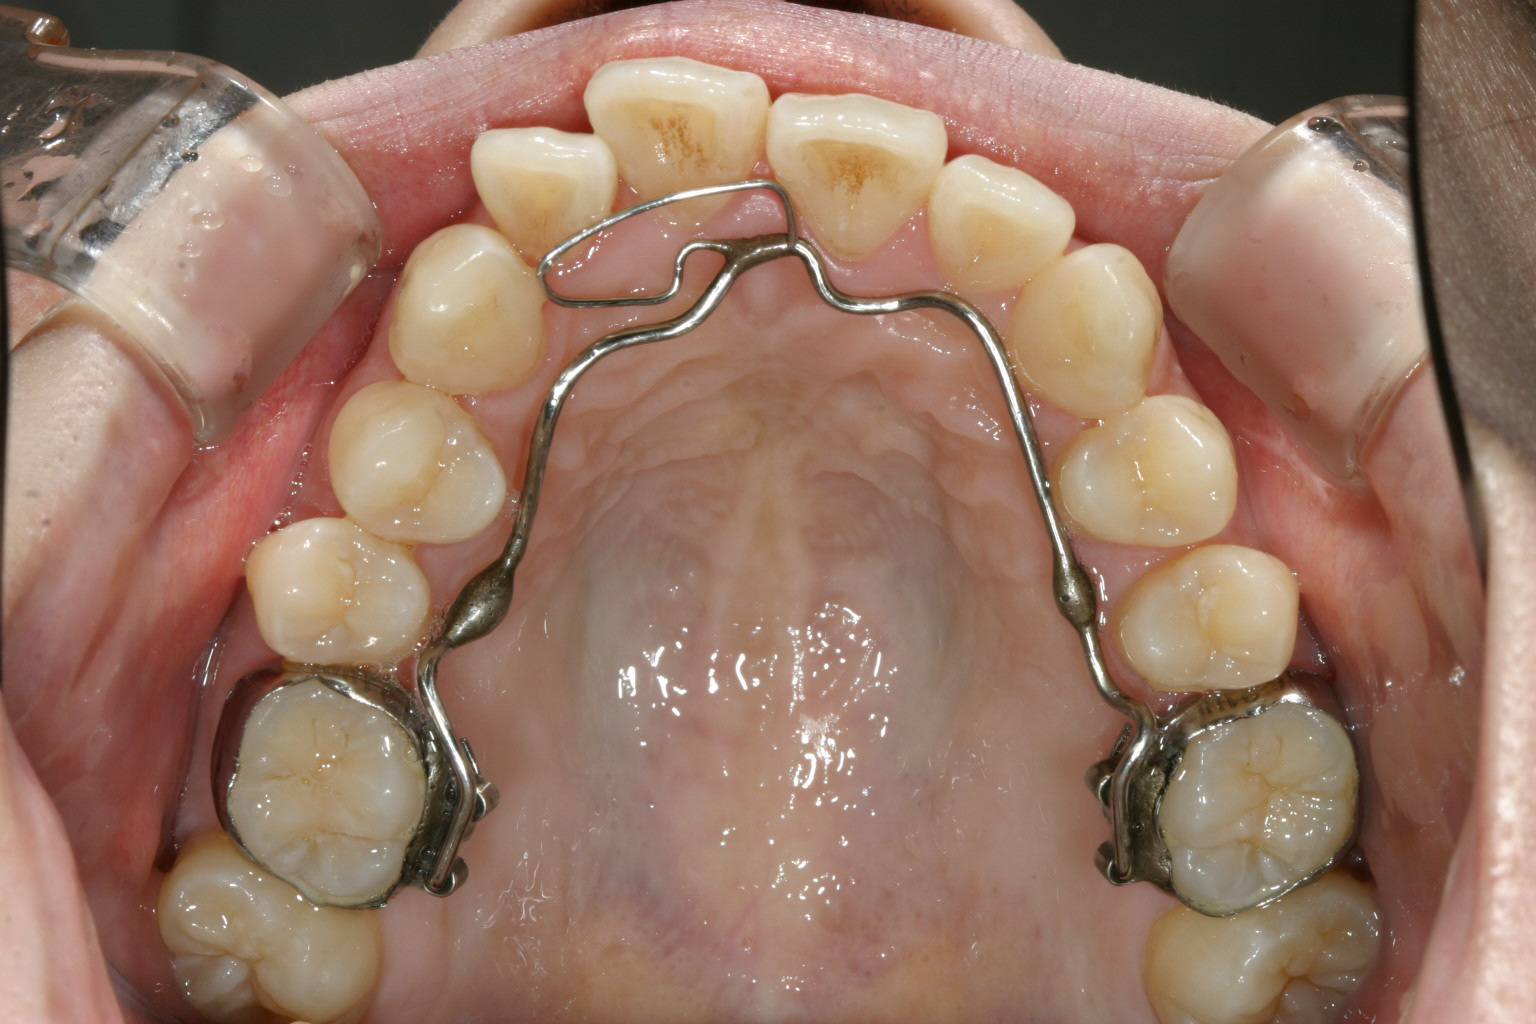

かなり古い症例で先ずリンガルアーチにてアーチの拡大と前歯の叢生 治療から始めました。

リンガルアーチにて少し裏から押しましたから少し出て来ました。